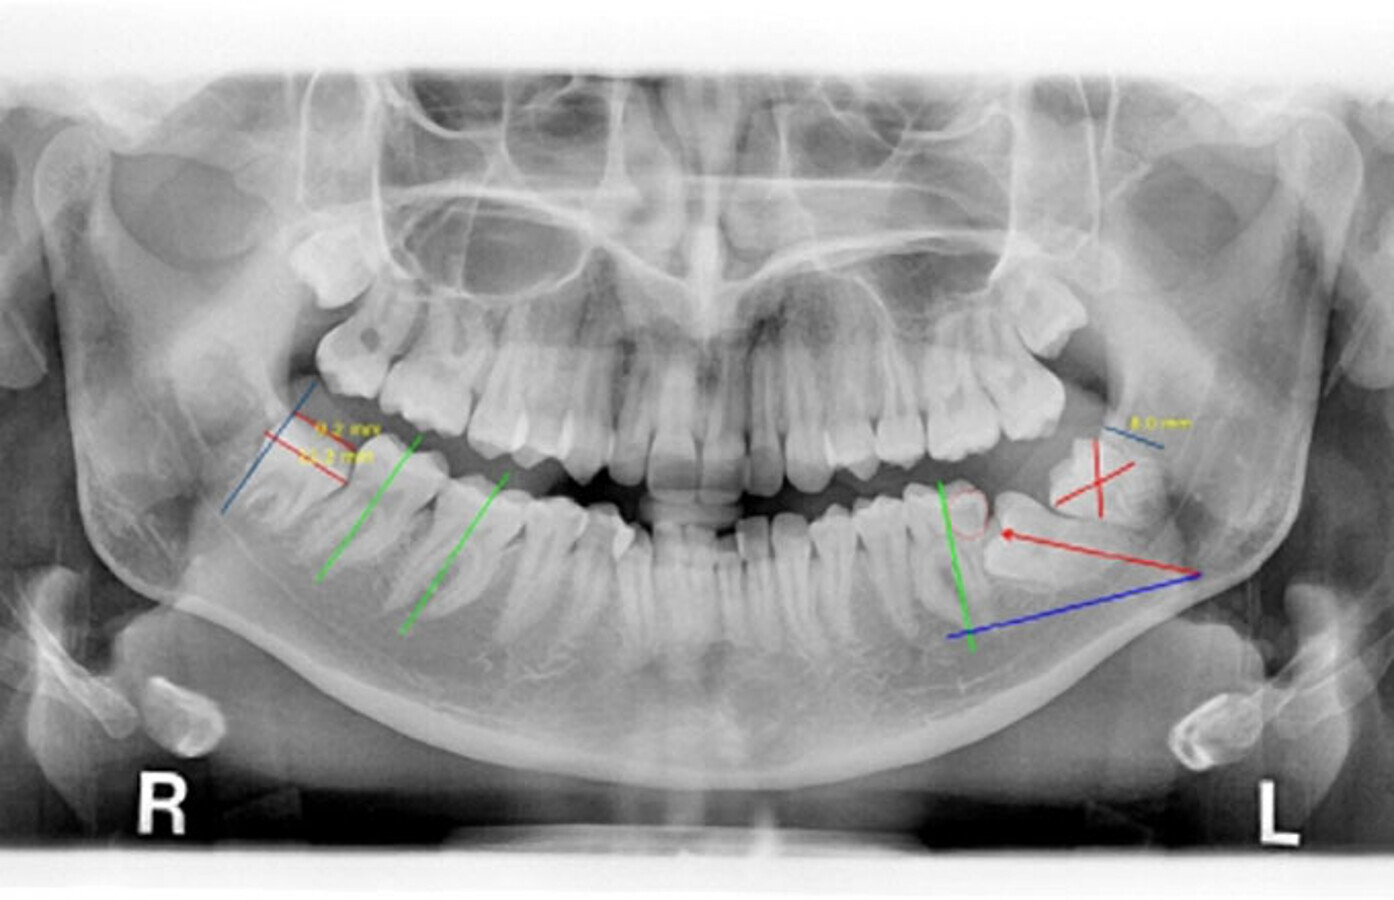

Molar 36 y 37 impactado horizontal.

El autor presenta un caso de un segundo y tercer molar inferior enclavados, “diente retenido que ha perforado el techo óseo, con apertura del saco pericoronario o no, y que puede hacer su aparición en la boca o mantenerse submucoso”, y su tratamiento ortodóntico-quirúrgico.

Los terceros molares inferiores retenidos constituyen aproximadamente un 35% de las retenciones dentarias. Sin embargo, los segundos molares inferiores retenidos sólo se encuentran en un 0,5% de las inclusiones.

Detalle de ortopantomografía.

Estudio de ortopantomografía